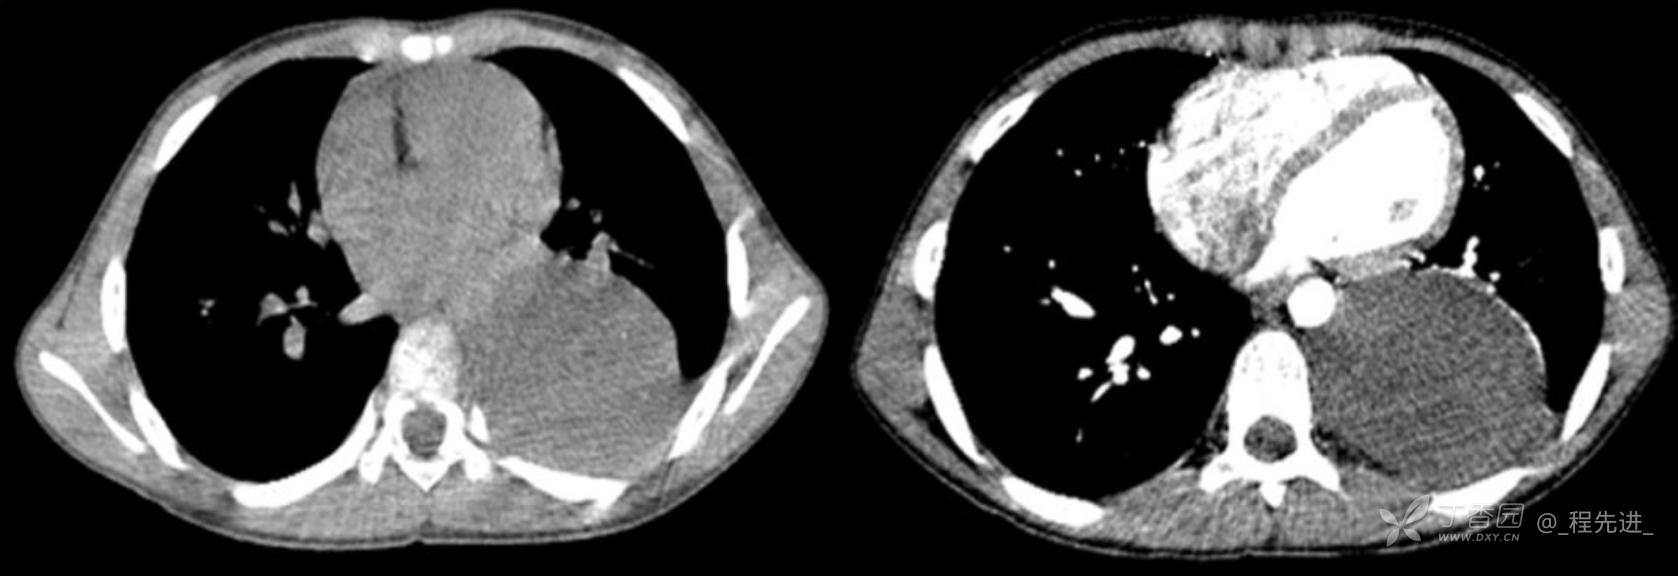

11月特别精彩病例|胸片示“左侧胸腔包裹性积液”,CT增强你诊断啥?【病理已公布】

呱呱叫了 等 3 位达人已点赞男,11岁,患儿因其爷爷近期在我院诊断“肺结核”,于外院行结核筛查,胸片示“左侧胸腔包裹性积液”,近期无咳嗽、发热、纳差、盗汗、乏力、胸痛、胸闷、气促不适,精神反应可,为求明确“左侧胸腔包裹性积液”病因,遂来我院门诊就诊,门诊以“胸腔积液查因”收住入院。发病以来,精神尚可食欲如常,大便如常,小便量如常,体重无明显变化

各项实验室检查均正常